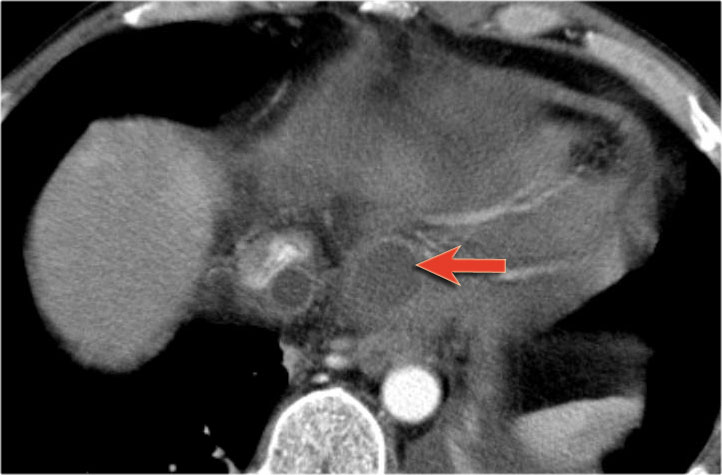

Hình ảnh CT cho thấy một nang lớn ở vùng thượng vị trên bệnh nhân có tiền sử viêm tụy cấp (Hình).

Lưu ý có thêm một ít dịch cổ trướng và dịch màng phổi.

Thành nang có ngấm thuốc.

CT cho thấy hai nang lớn ở bệnh nhân nữ 45 tuổi có tiền sử chấn thương (hình).

Lưu ý hình ảnh thâm nhiễm mỡ trong khoang sau phúc mạc (mũi tên).

Kết hợp đặc điểm hình ảnh với tiền sử lâm sàng, rất có khả năng đây là các nang giả tụy do chấn thương.

Hầu hết các nang giả tụy xuất hiện ở vùng quanh tụy, tuy nhiên hiếm gặp hơn, chúng có thể lan vào trung thất.

Bệnh nhân này bị viêm tụy mạn tính.

Lưu ý các vôi hóa ở đầu tụy (mũi tên cong).

Có nhiều nang giả tụy lan dài vào tận trung thất, gây chèn ép tim (mũi tên đỏ).